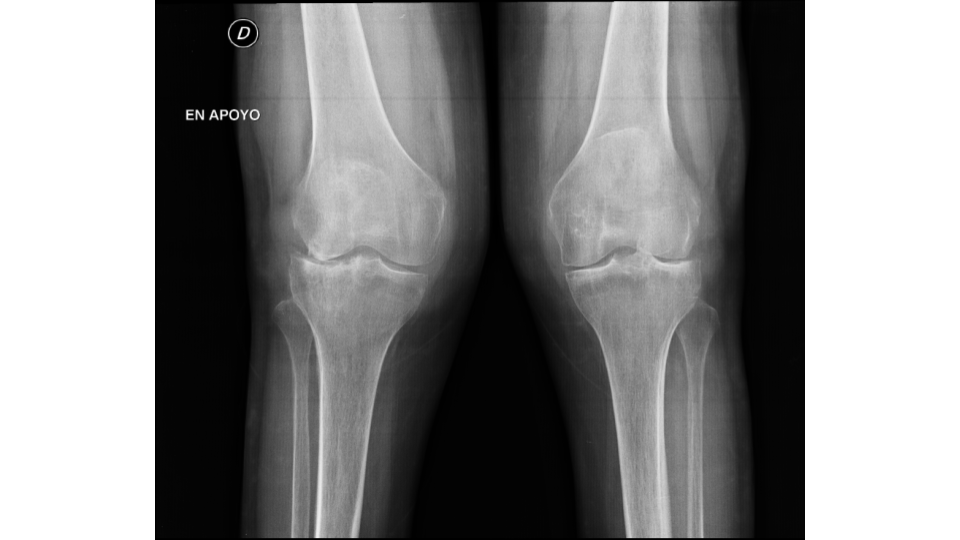

Se analizó un total de 36 prótesis en 32 pacientes. De este total, 25 (78 %) fueron de sexo femenino y 7 (22 %), de sexo masculino. Cuatro pacientes presentaron reemplazo bilateral (Figs. 1, 2 y 3).

Figura 1. Radiografía anteroposterior de ambas rodillas que muestra genu valgo bilateral secundario a artrosis.